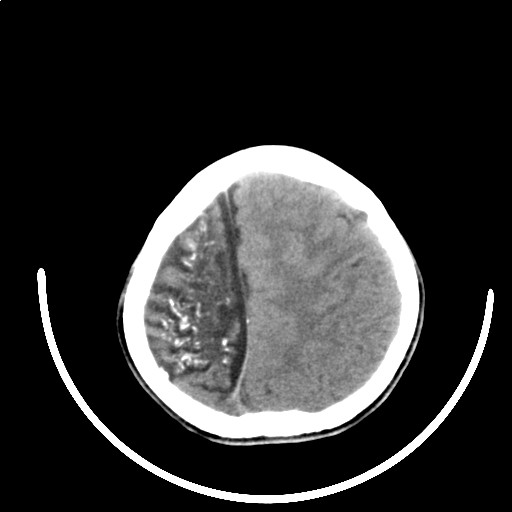

标题: PED3416:F,12Y,智力下降,学习成绩差,8个月时发过高烧。

右侧半球萎缩,软化,多量脑回样钙化,考虑颅面血管瘤病,建议dsa检查

右侧半球萎缩,软化,多量脑回样钙化,同侧颅盖板障增宽,考虑颅面血管瘤病,建议dsa检查与化脓性脑膜炎后遗改变鉴别。